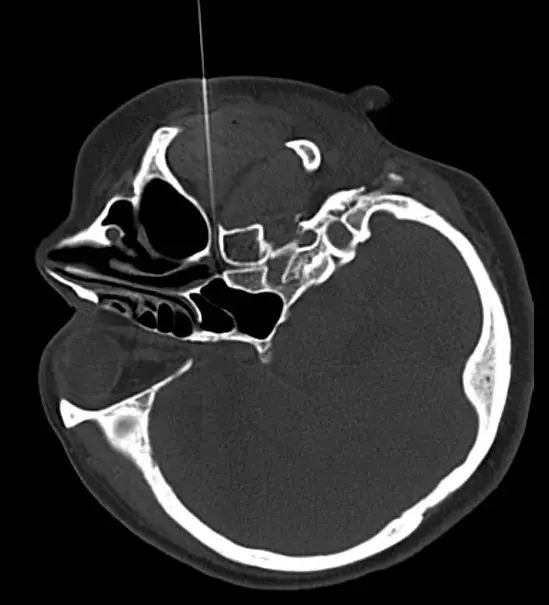

图为赵女士在CT精准引导下进行蝶腭神经节射频治疗,此治疗技术风险小、痛苦小、治疗时间短、疗效显著,几乎无副作用等优点。

浙江温岭连恩青因过敏性鼻炎术后空鼻症,导致杀害了耳鼻喉科王云杰主任的事件,相信大家历历在目。尽管最后杀人者被判了死刑,但这种一病两命的结局是谁都不愿意看到的!那么连恩青为什么要杀害为他治病的医生呢?事情还得从连恩青所患的过敏性鼻炎疾病说起!这是一种常见病和多发病,主要是由过敏物质,如花粉,雾霾,灰尘,异体蛋白,甚至是空气质量和温度引起的。有的根本就查不到过敏源,其症状有鼻塞,鼻痒,流涕,打喷嚏。更有甚者晚上睡觉只能张口呼吸,严重影响睡眠质量。所以,它对人们的日常生活影响巨大,且常影响你的公众社交形象!赵女士就是一位患此病二十多年的患者,用她自己的话说这么多年来医院没少去,药没少吃,罪没少受。但就是效果不大,有医生建议她手术,她眼前立即就会浮现连恩青的空鼻症事件。终于一次偶然的机会,经朋友介绍,她找到了世界中医药联合会疼痛与康复委员会常务理事,副主任医师梁文军医生,采用国际先进技术一一CT引导下蝶腭神经节脉冲治疗过敏性鼻炎。赵女士半信半疑地在梁主任确保治疗安全的前提下接受治疗。真是医治有缘人,赵女士在CT引导下大概45分钟基本无任何痛苦就结束了治疗。别说,还真神奇,赵女士现在症状基本消失,只是偶尔过度疲劳或感冒后还有些许症状,咨询了梁大夫说大概还要3~6个月的恢复期。原来赵女士不带两三包纸巾几乎不敢出门,现在基本不再为商务谈判时鼻胧口水影响公众形象而操心了!那么梁文军医生又是如果学习和掌握了这门高科技技术的呢?原来梁医生师从于北京中日友好医院杨克勤教授,而杨教授早年东渡日本,主要从事三叉神经痛,癌症痛,顽固性头痛,颈肩腰腿痛,带状疱疹痛及过敏性鼻炎的病因研究和治疗!而蝶腭神经节正是支配鼻粘膜的主要神经,当鼻粘膜受到过敏源刺激后,交感神经兴奋,使鼻粘膜充血水肿,导致流涕,鼻塞,鼻痒,打喷嚏,甚至呼吸困难!而蝶腭神经节的治疗既不影响嗅丝,又不会导致鼻腔干燥而产生空鼻症!这是手术有创治疗无法避免的!在杨教授和梁医生亲手诊治的上千例患者中,显效率在95%以上。无一例出现连恩青后遗症!那么这种既安全又有效的治疗方法,到哪里可以找到梁医生和杨教授呢?亲们,福利来了: